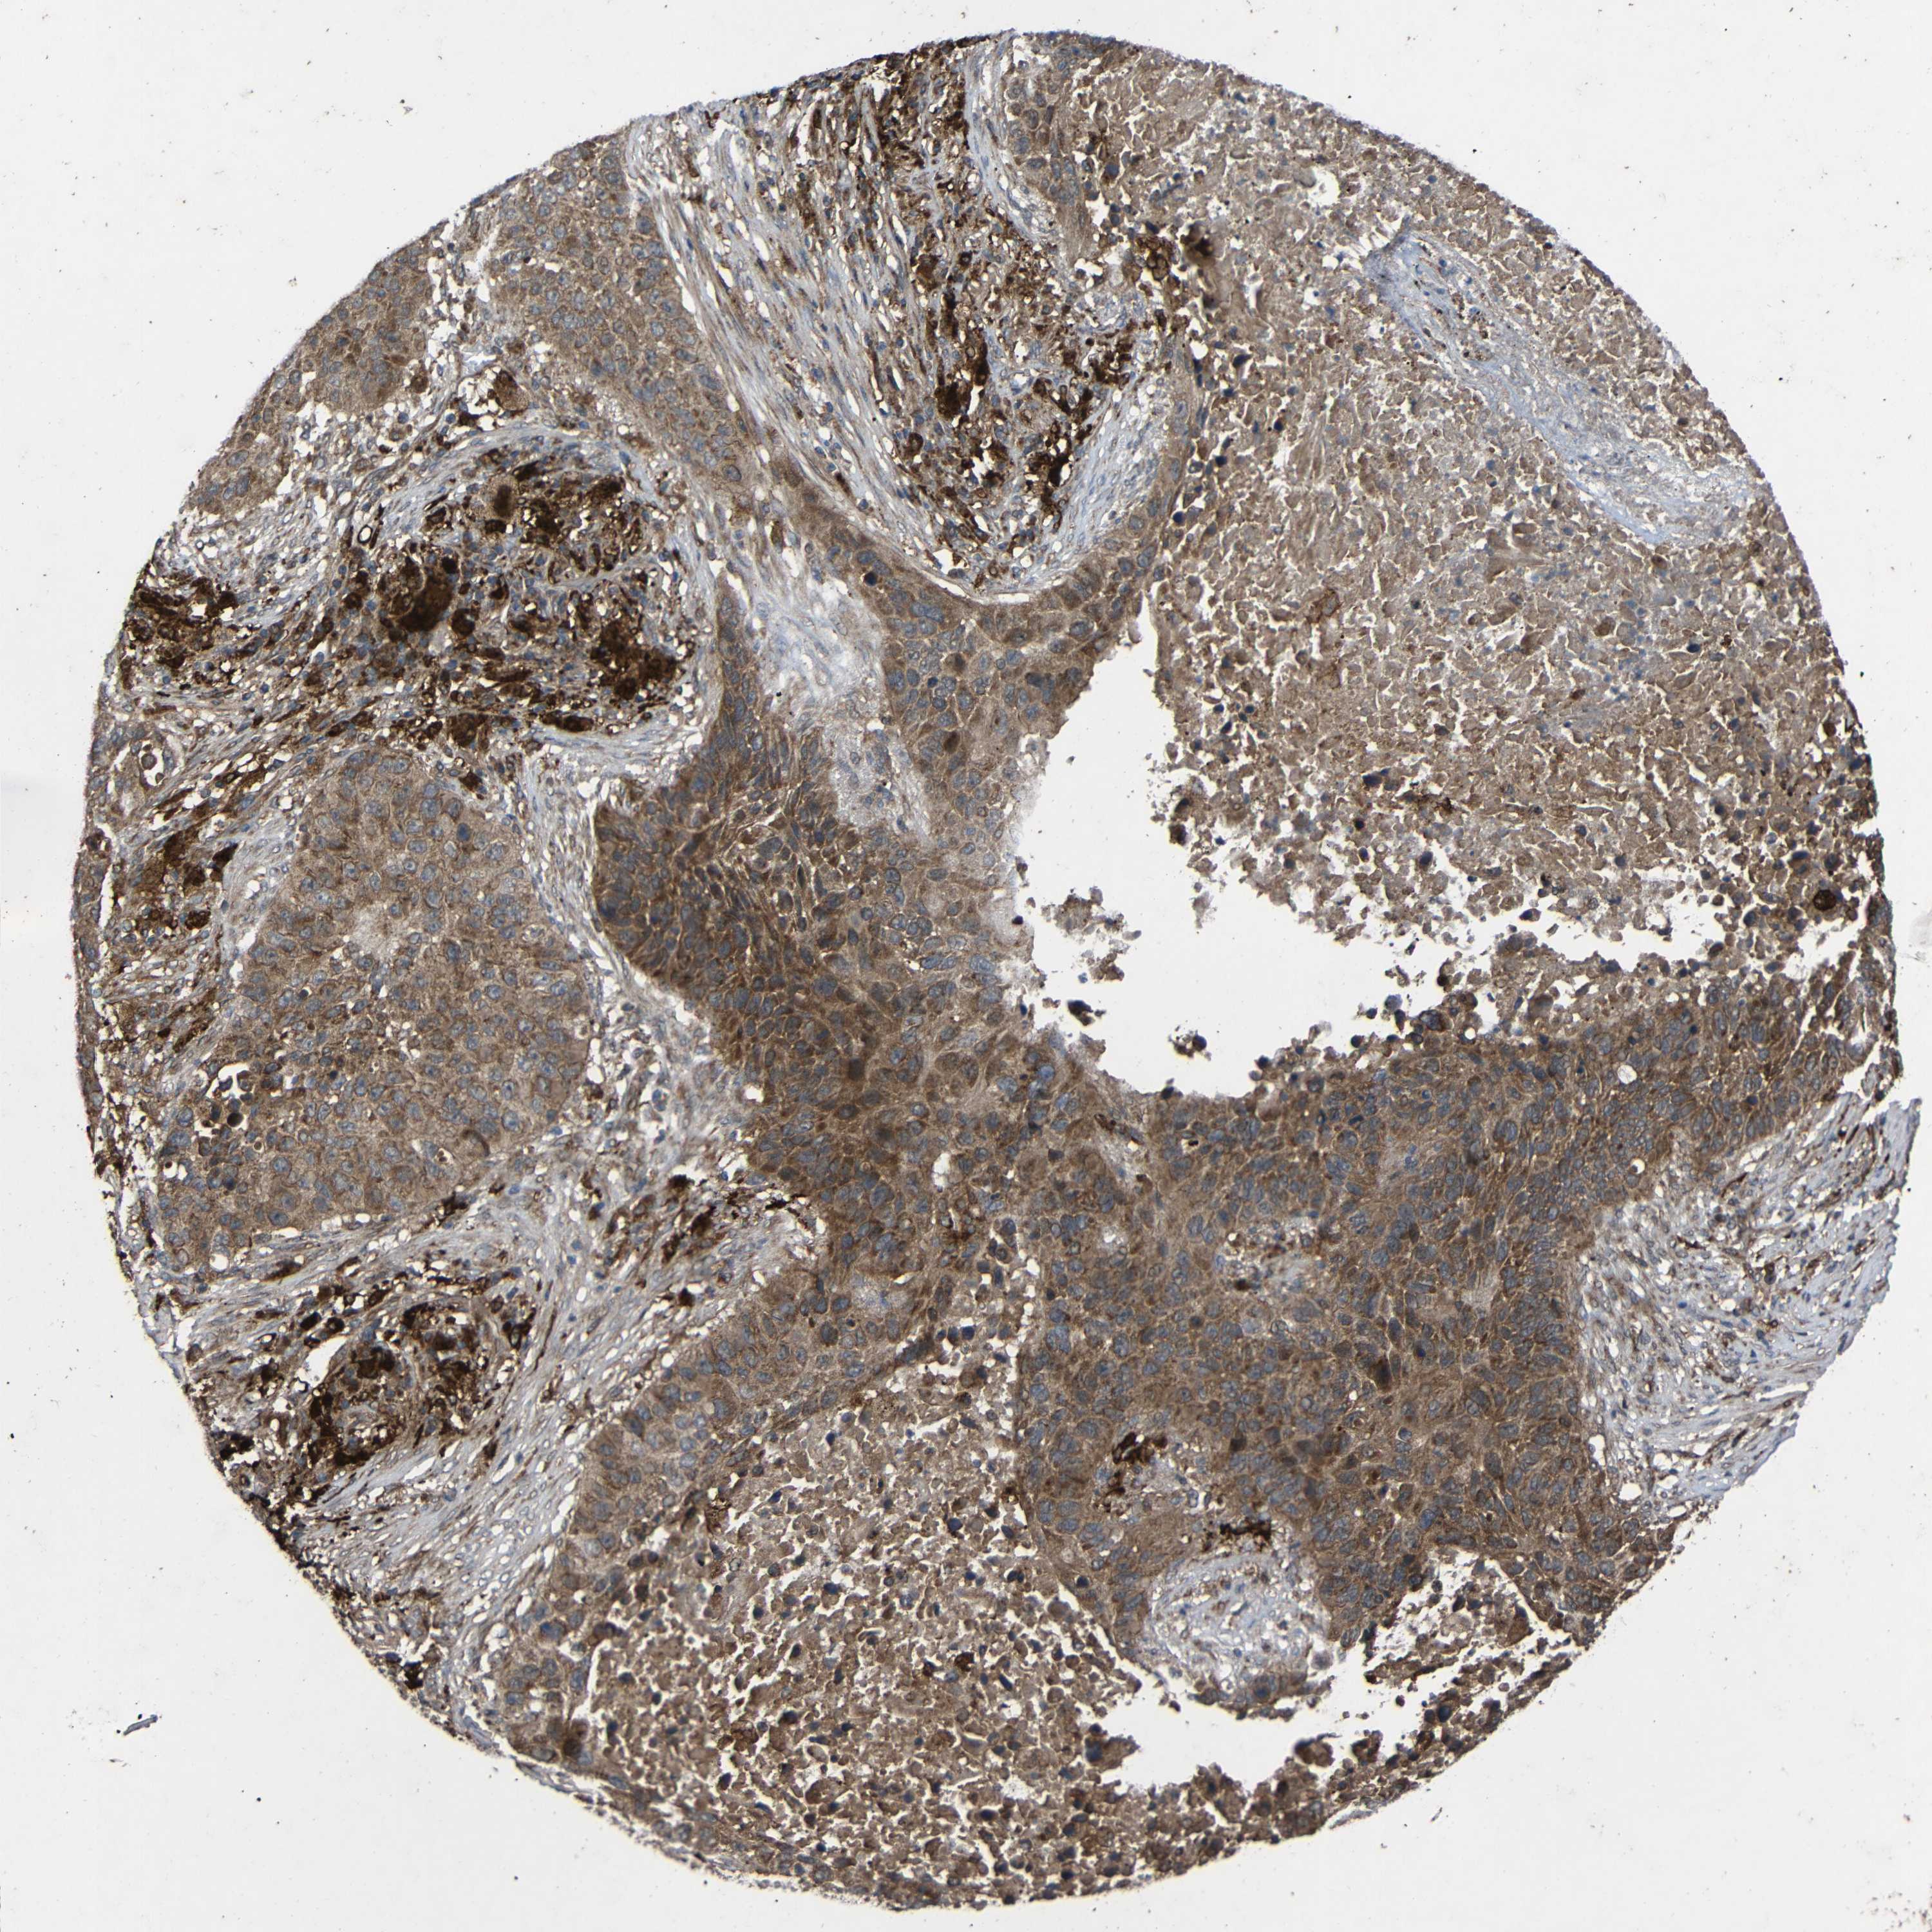

LUNG SQUAMOUS CELL CARCINOMA (TCGA) - Interactive survival scatter ploti

C1GALT1 is not prognostic in Lung Squamous Cell Carcinoma (TCGA)

: 10.63

Average pTPM 16.9

Number of samples 489